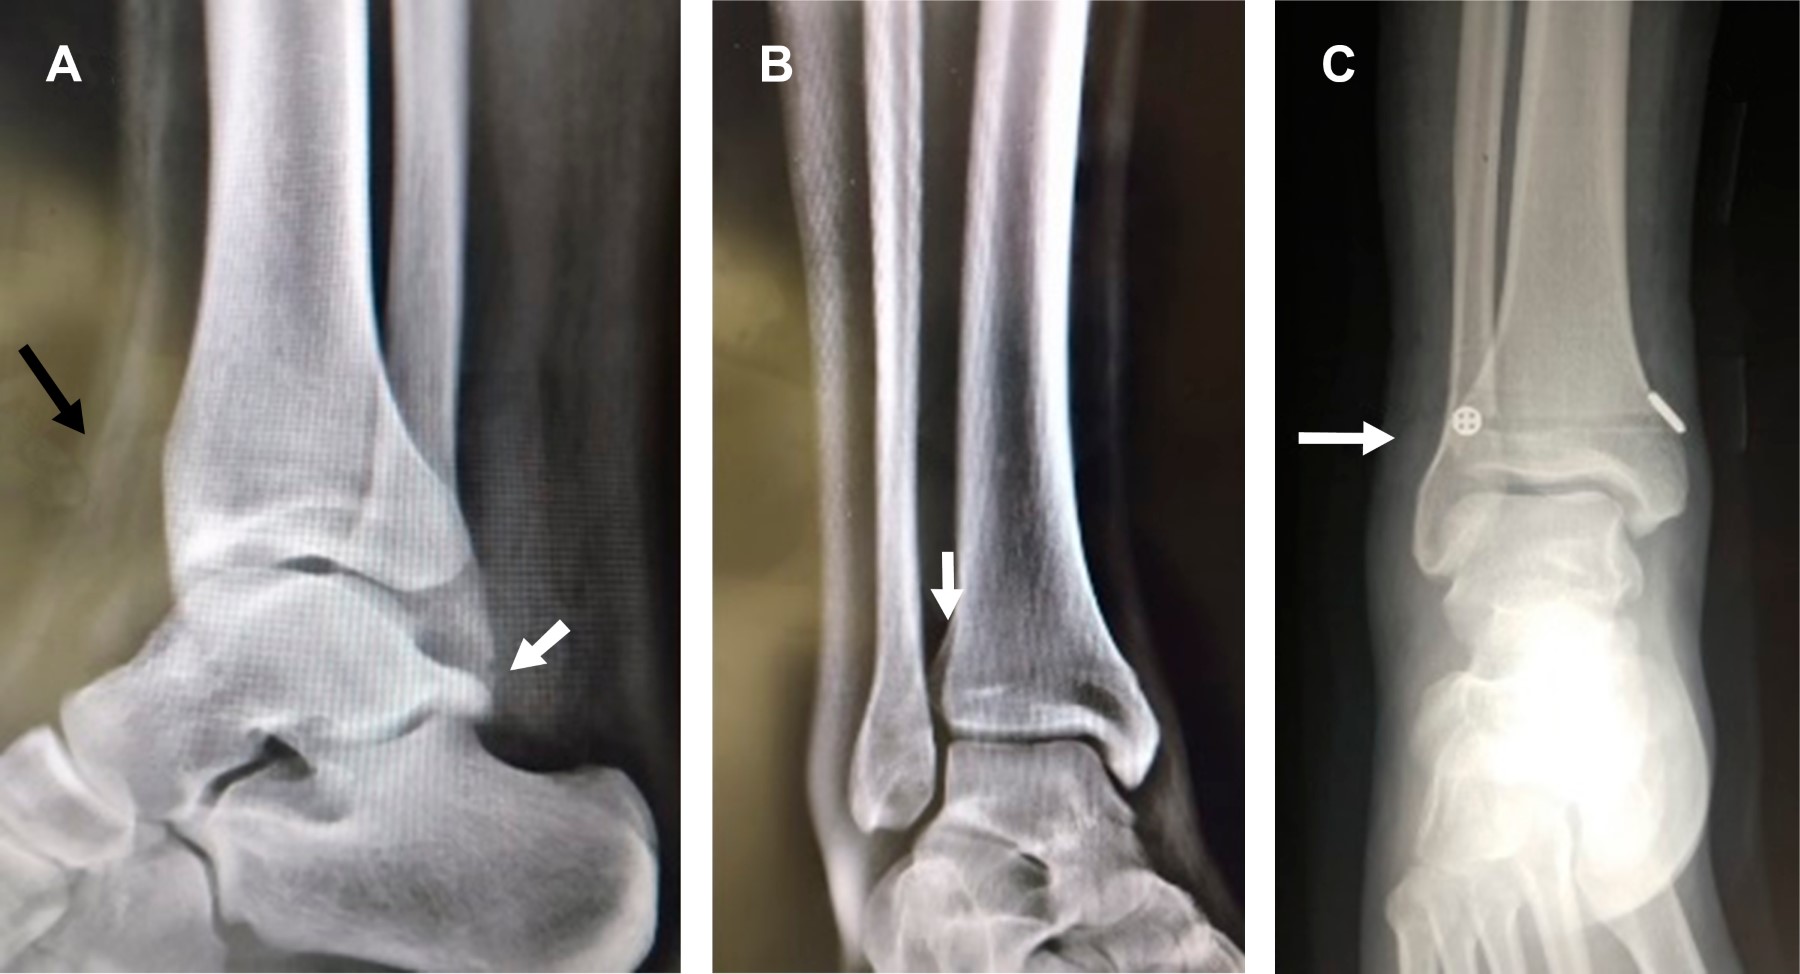

Masculino de 25 años que tres semanas atrás sufrió inversión del tobillo derecho durante la marcha, se automanejó con férula AeroCast por dos semanas, permaneciendo asintomático por tres días en que inició trote de 5 km, presentando al final dolor intenso y edema de cara anterior de tobillo. A la exploración dirigida: edema de la zona, dolor intenso durante pruebas de Hopkinson y de estrés en rotación externa del pie, por lo que con diagnóstico de lesión de la sindesmosis tibioperonea inferior se solicitan radiografías (Figura 1A y B) y resonancia magnética (Figura 2), confirmando diagnóstico. Se efectuó fijación de la sindesmosis con el sistema TightRope, que ancla los extremos de la tibia y el peroné mediante un cordón de polietileno trenzado (Figura 1C) y reconstrucción de la cápsula articular. Se colocó inmovilizador de tobillo y se canalizó a las tres semanas a rehabilitación.

Figura 1